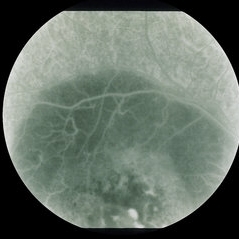

This eight year old white male was referred for evaluation of a lesion in the posterior pole of the right eye. The patient was born one month premature and received oxygen for four days at birth. He suffers from migraines and takes Periactin, 1/2 teaspoon at bedtime for asthma. The vision is 20/100 best corrected on the right and 20/20 on the left. There is a 7 prism diopter esotropia distance and near and no significant refractive error. The left fundus is completely negative. The slit lamp examination, pupilary reactions, and intraocular pressure were unremarkable in both eyes.